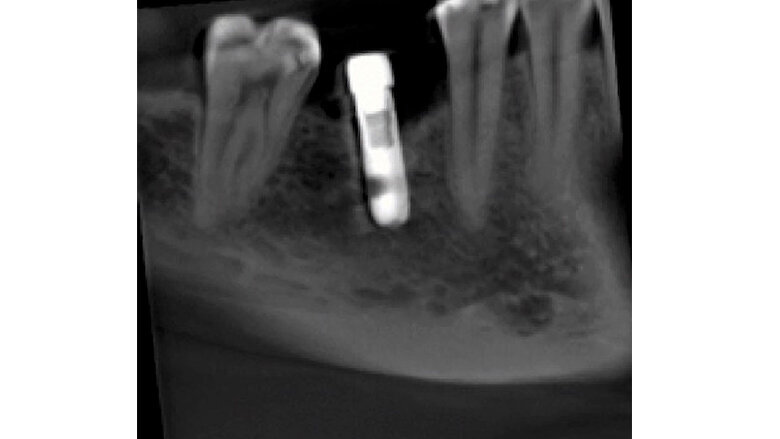

En las imágenes tomográficas (Figuras 2,3) se observa una zona hipodensa en la parte distal del implante, que tiene un halo alrededor del mismo. A los 15 meses, esta imagen hipodensa había desaparecido (Figuras 4,5,6).

Fig 2. Tomografía inicial. En distal del implante se observa un halo hipodenso desde el reborde, que se dirige a la parte apical, lo que es compatible con peri-implantitis; a nivel del reborde óseo mesial y distal observamos pérdida ósea. Como indican las flechas, se realiza una descontaminación con láser de erbio cromo YSSG alrededor del implante que remueve todo microorganismo.

Fig 3. Tomografía a los 4 meses. El halo hipodenso en la parte distal del implante ya no está tan marcado, sobre todo en la parte inferior del implante, es decir, que hubo una reduccion de esta zona; además, observamos un leve aumento de la densidad ósea en la zona mesial y distal del implante a nivel del reborde. Se realiza terapia de fotobioestimulacion con láser de diodo en la zona.